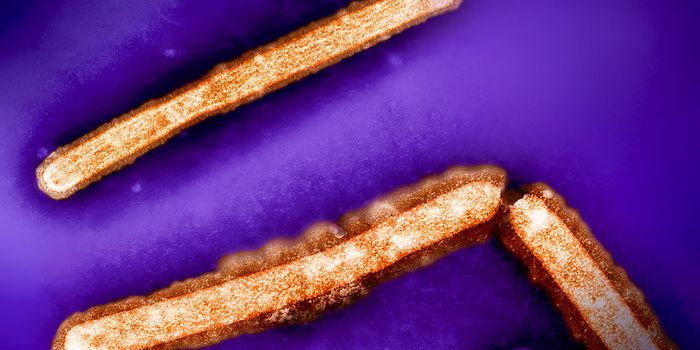

AUG 06, 2024MicrobiologyIndia is experiencing the most severe outbreak of a disease known as Chandipura virus in decades. Previous outbreaks hav ...